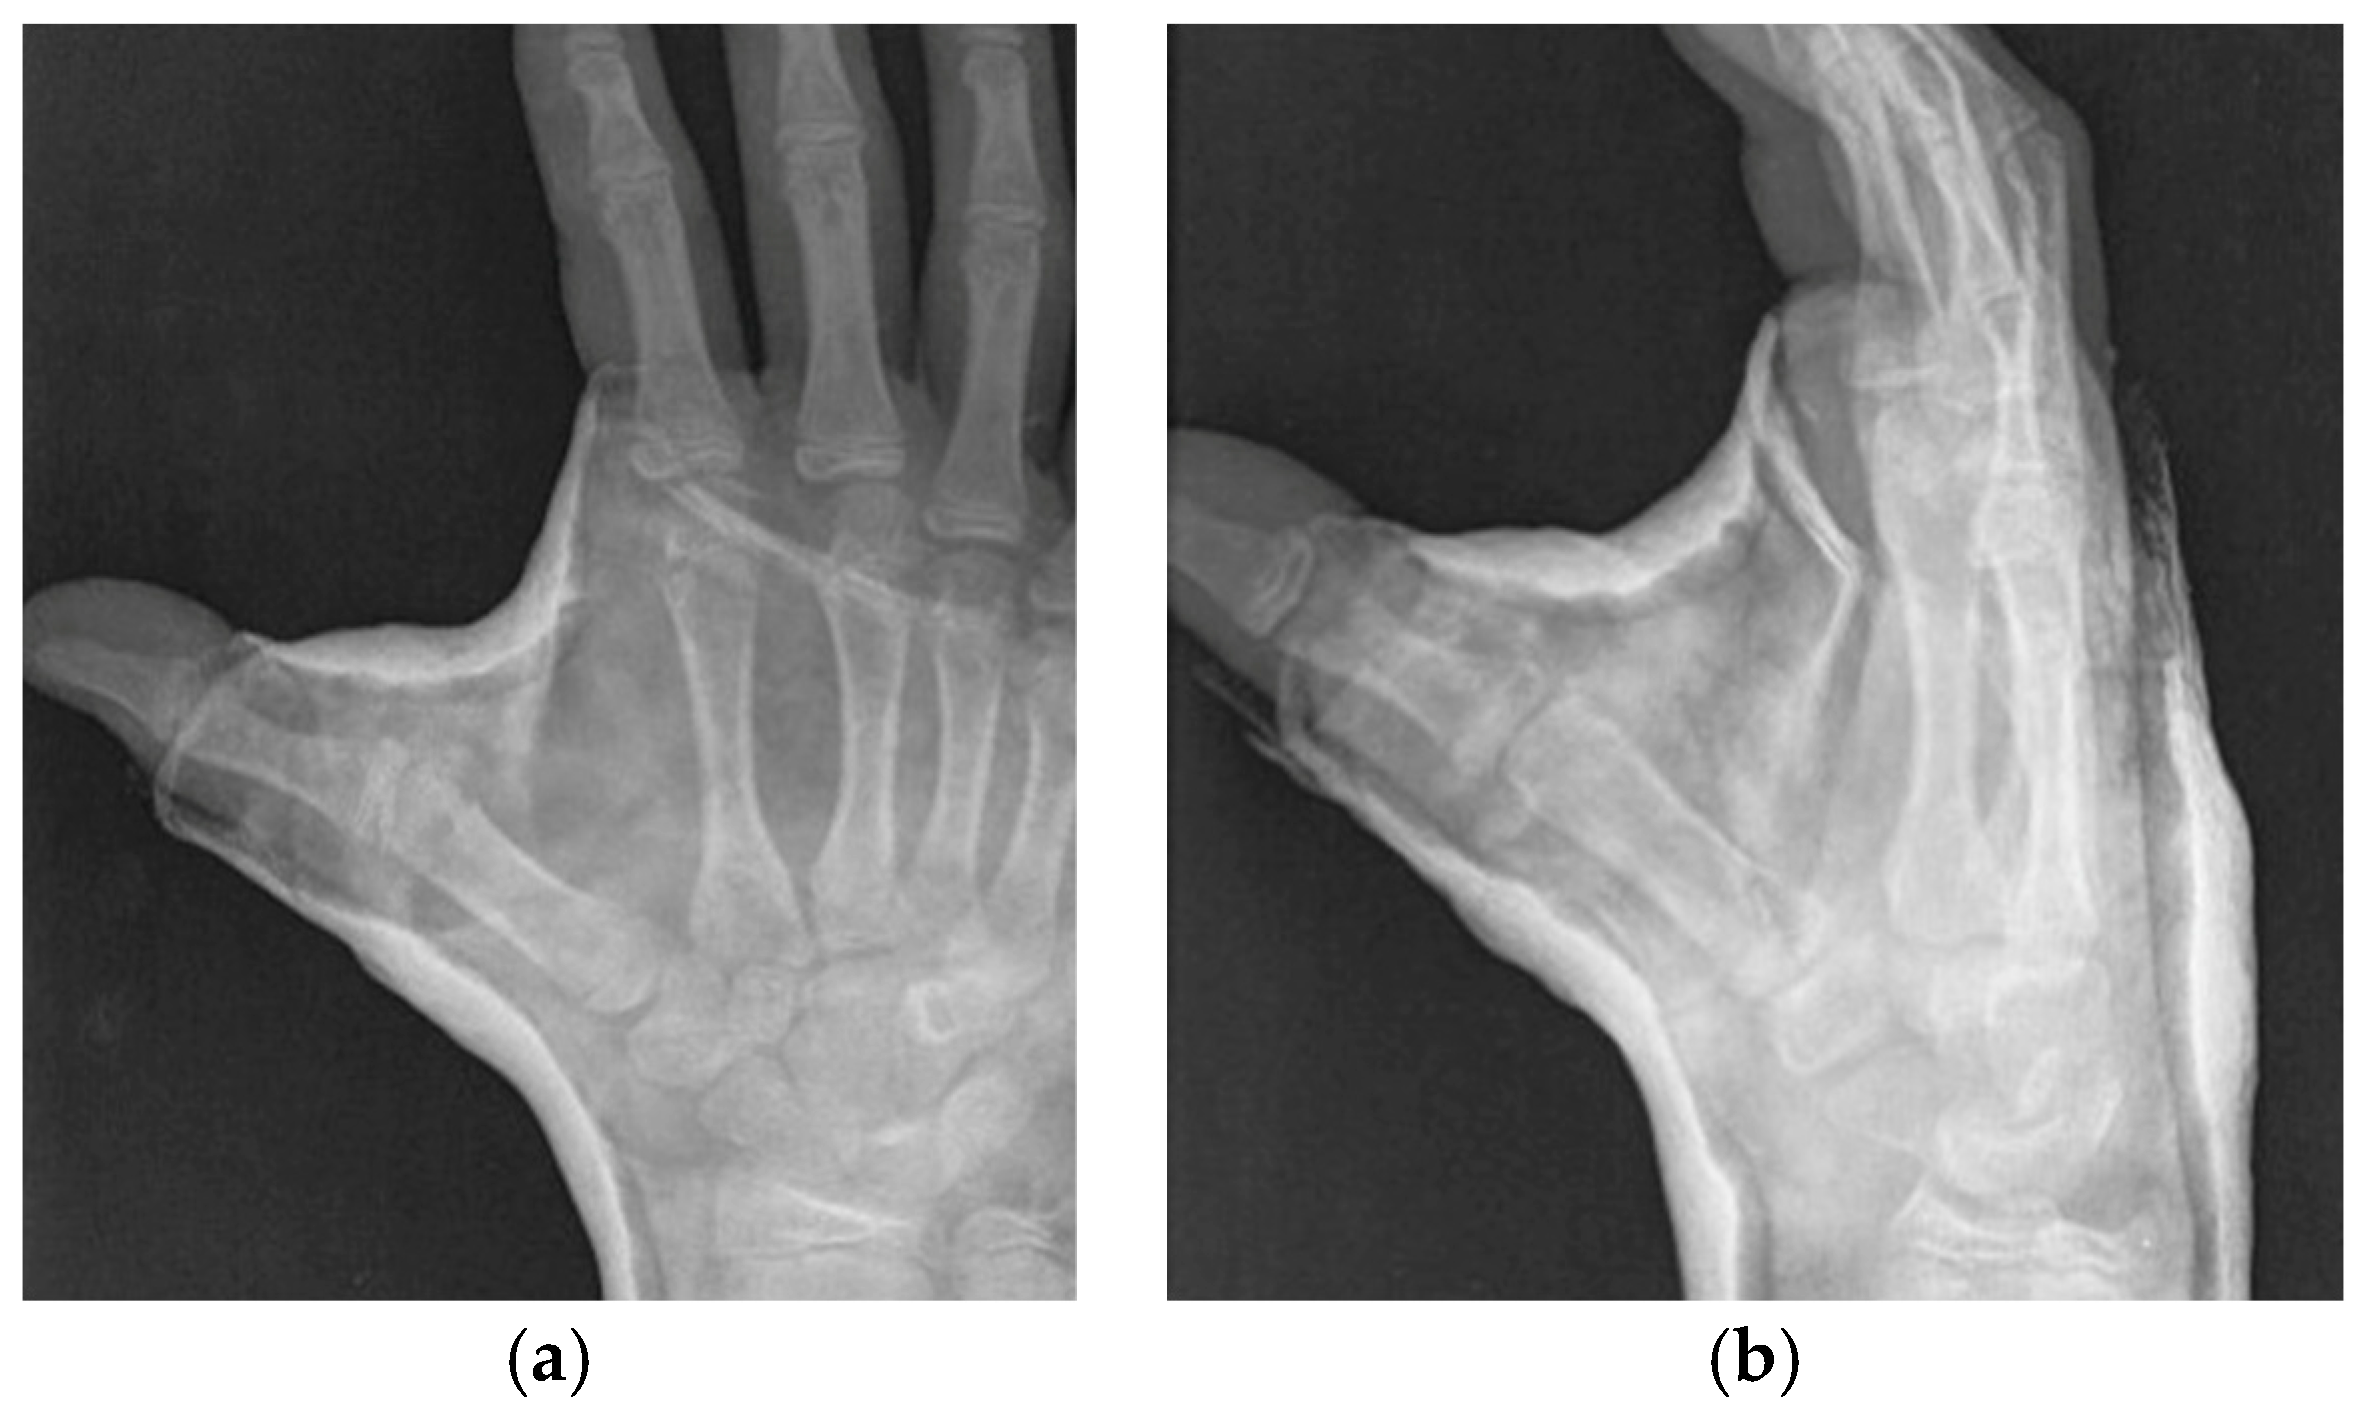

- Roberts projection—strict AP view of the TMC joint. Roberts proposed forced pronation of the wrist and forearm to compensate for the obliquity of the longitudinal axis of the TMC joint in relation to the anatomical axis of the hand. This projection provides a strict profile of the interline of the trapeziometacarpal and scaphotrapezial joints and allows better visualization of the trapezium without carpal superimposition [21] (Figure 2a).